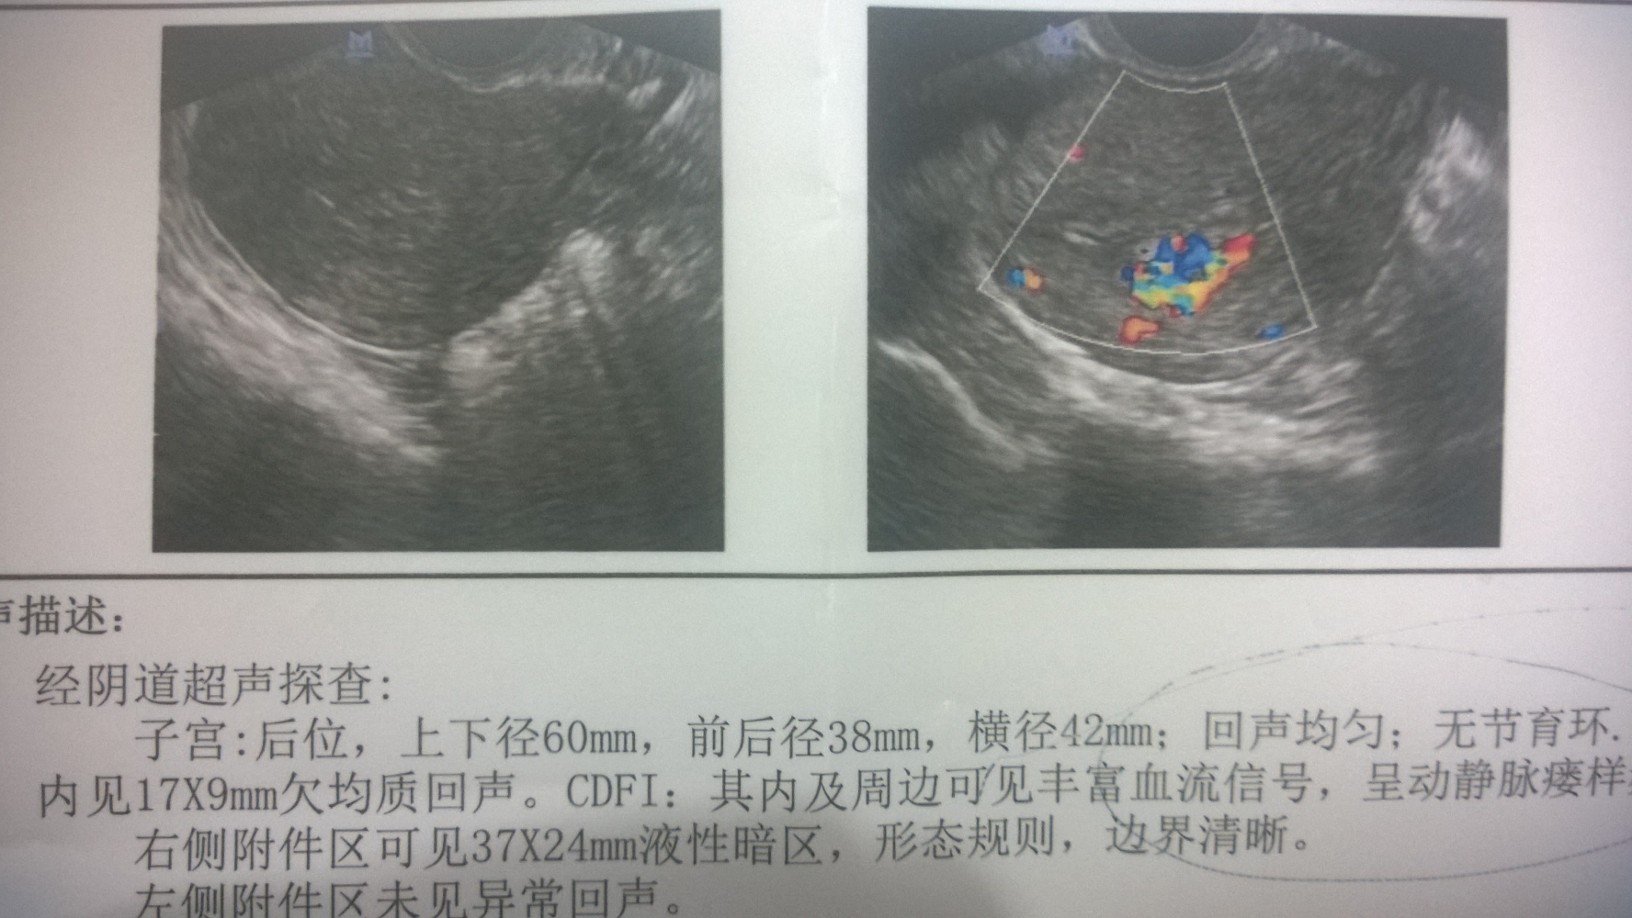

药流满月后月经结束一星期了,现在就早起还来很少血,颜色呈浅红色 做了彩超,怀疑有动静脉瘘形成